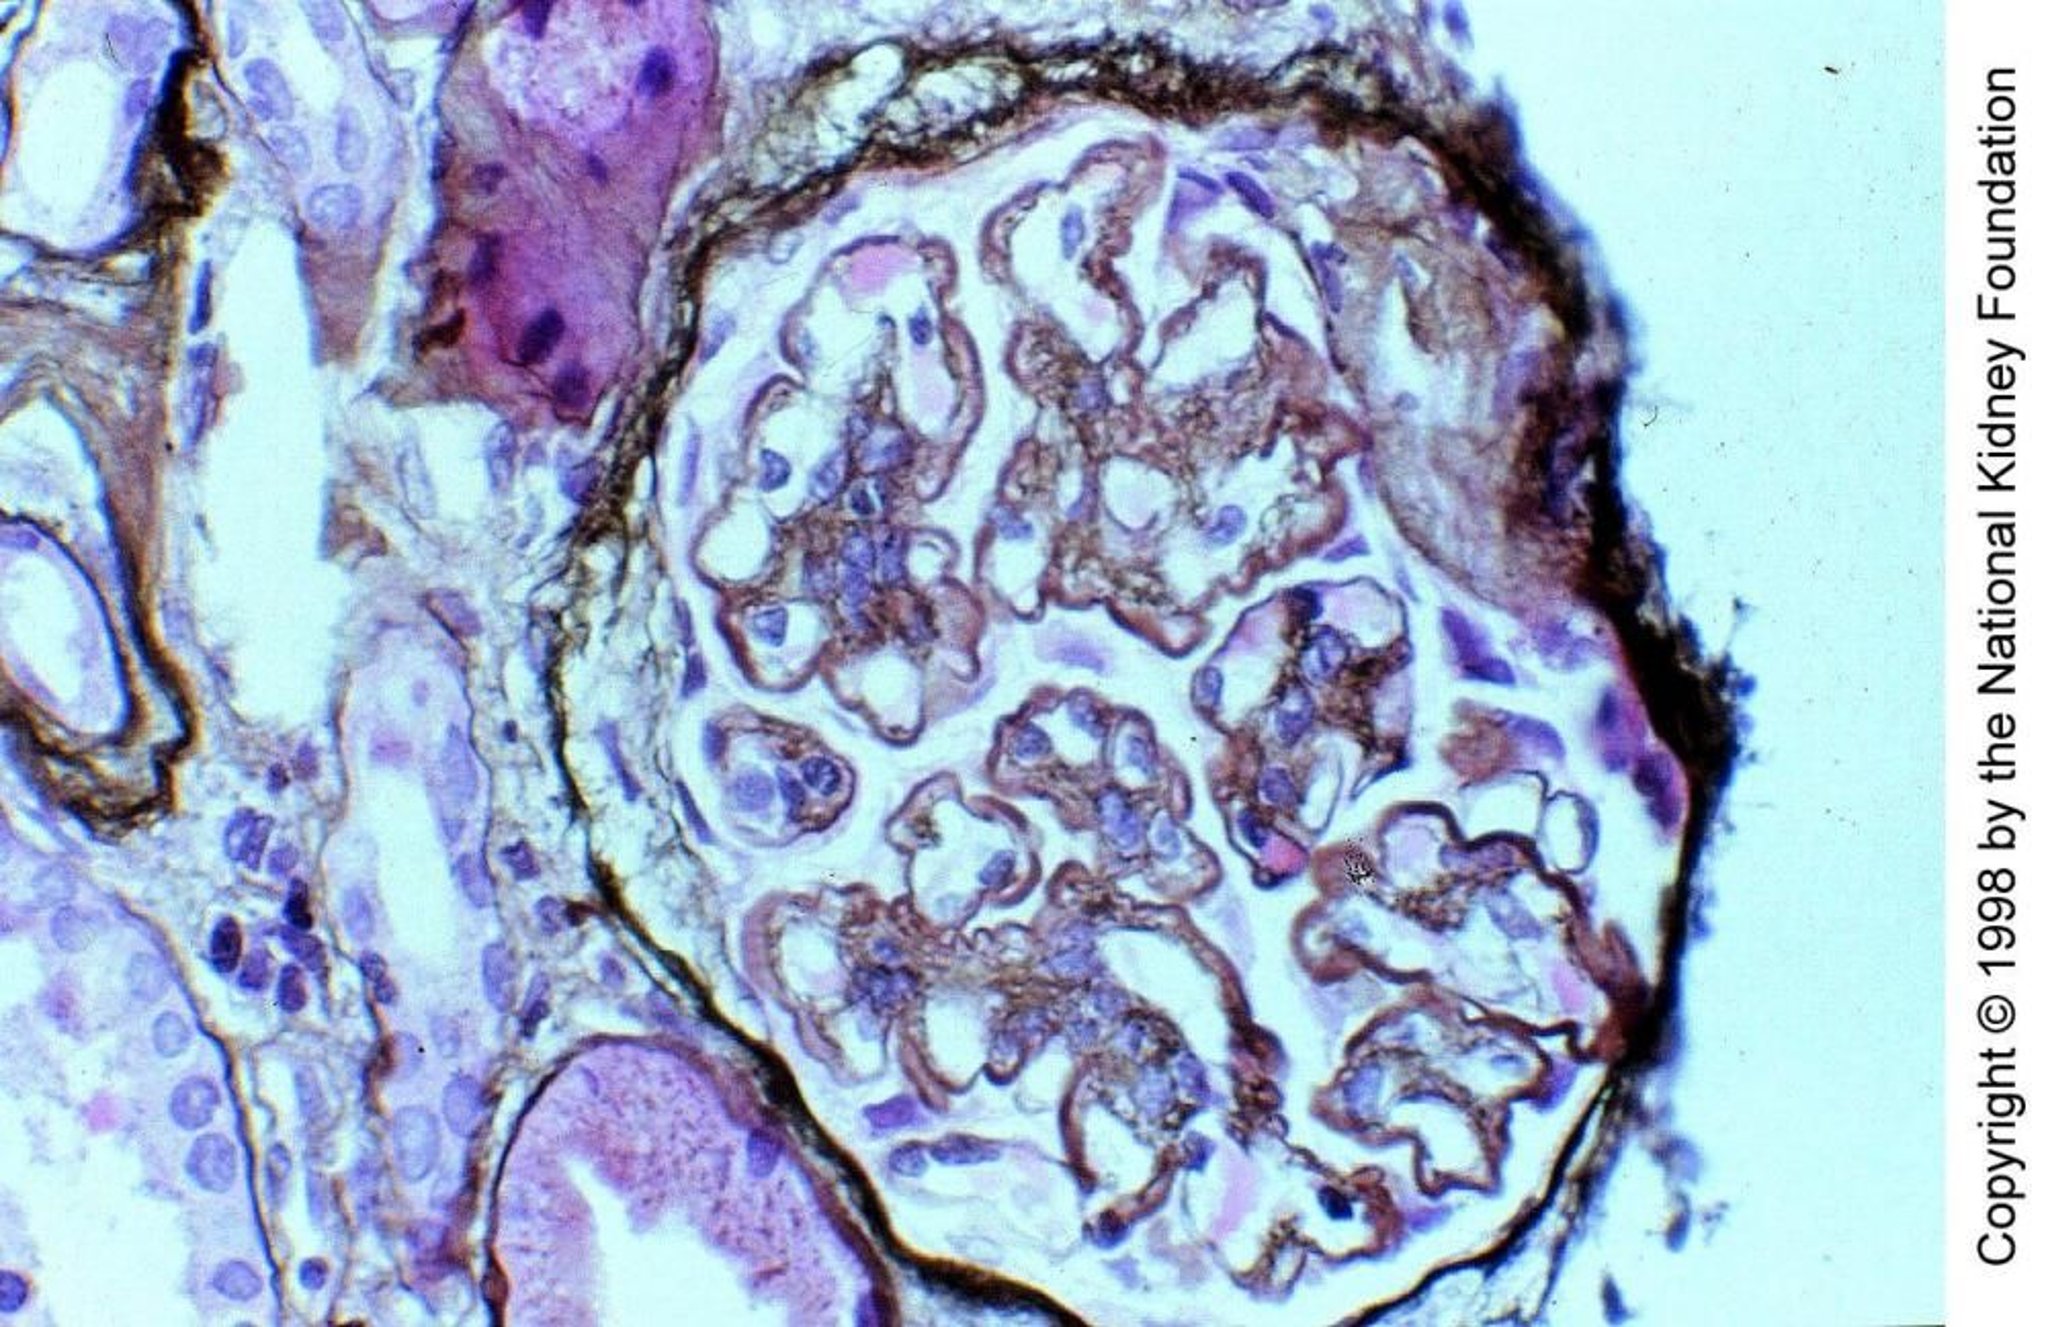

Membranoproliferative glomerulonephritis (MPGN) is characterized by a pattern of glomerular injury on light microscopy, including hypercellularity and thickening of the glomerular basement membrane. The clinical presentation usually consists of mixed nephritic and nephrotic features. Cause is idiopathic or secondary to another disorder. Diagnosis is by renal biopsy. Treatment is directed at the underlying disorder, when present. For patients with idiopathic disease, treatment may be supportive or include corticosteroids and other immunosuppressive agents.

Membranoproliferative glomerulonephritis (MPGN) is characterized histologically by glomerular basement membrane (GBM) thickening and proliferative changes on light microscopy.

• Membranoproliferative glomerulonephritis (MPGN) is a pattern of glomerular injury with characteristic findings on light microscopy, including hypercellularity and thickening of the glomerular basement membrane.